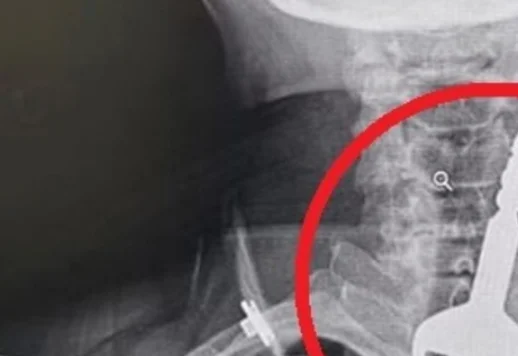

המפתח התגלה בצילום רנטגן שעבר, והוא הראה כי המפתח פשוט 'נתקע' בקנה הנשימה שלו, ולא איפשר לו לנשום בצורה תקינה.